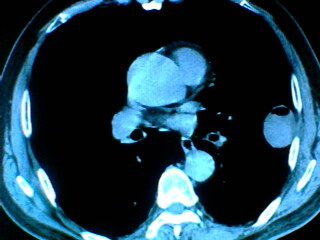

老年男性患者,右侧胸疼1月余(不是左侧),无其他症状

左肺外周类圆形病灶,其内低密度,可见液平及气影,周围肺文理见渗出样变,考虑左肺外周带肺脓肿。

左肺舌叶胸膜下卵圆形囊性肿块,内有液-气平面,邻近胸膜无增厚,没有肺窗,周围情况显示不清,考虑胸膜下肺囊肿并感染,病人年龄较大,有胸痛应警惕其他,但神经源性肿瘤暂不考虑。